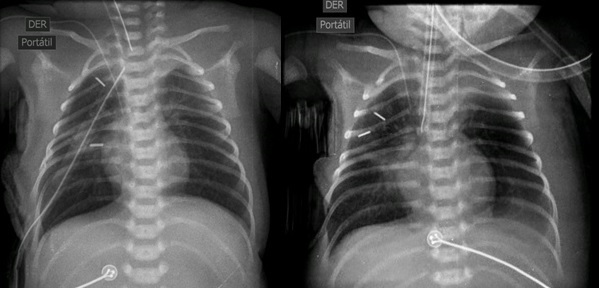

Technique: In the first step of the procedure, we mobilized the proximal and distal esophageal segments and placed pledgets on their ends. We then inserted prolene sutures through the full thickness of the esophagus, and reinforced it with a titanium clip (Fig. 1). The long ends of the sutures were externalized through the chest wall for traction. After 5 days, we began the esophageal elongation process at the bedside by gradually placing several segments of feeding tubes under the sutures (Fig. 2). We monitored the progress of esophageal lengthening with chest x-rays, using the titanium clips as a guide for the esophageal ends (Fig. 3). Once the distance between the esophageal segments was approximately the length of a vertebral body, we restored the esophageal continuity.

Esophageal elongations were continued until the radiographs showed a distance of 1 vertebral body between the esophageal ends. This ensured the lack of tension upon the anastomosis, reducing the risk of suture dehiscence. The stage 2 procedure could then be performed. Two thoracotomies were required in our three cases, similar to Bairdan et al's report in their primary Foker process (FP) cases, with a mean of two thoracotomies in 27 patients. [7]

To ensure even tension on the esophageal ends during traction and to monitor the lengthening progress, we utilized pledgeted sutures reinforced with a titanium clip at the end of both esophageal pouches. This approach was also employed by Bairdan et al [7]. The use of titanium clips, which are radio-opaque and easily visible on X-rays, allowed for clear visualization of the clips and accurate assessment of the extent of lengthening. An animal model experiment has shown that using pledgeted sutures with double titanium clips is better than using simple sutures to prevent complications during the Foker technique. This is because they help prevent dislodging of the traction suture, which can be a problem during esophageal elongation. [8]

Figure 3

Radiographs were conducted daily to monitor the narrowing of the gap by the approximation of the titanium clips.